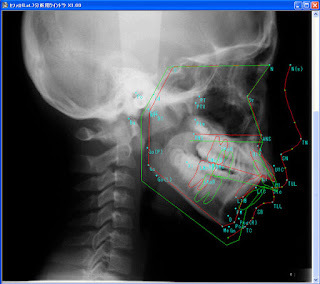

③レントゲン撮影

(パントモX線・頭部X線・頭部X線規格写真正面側面など)